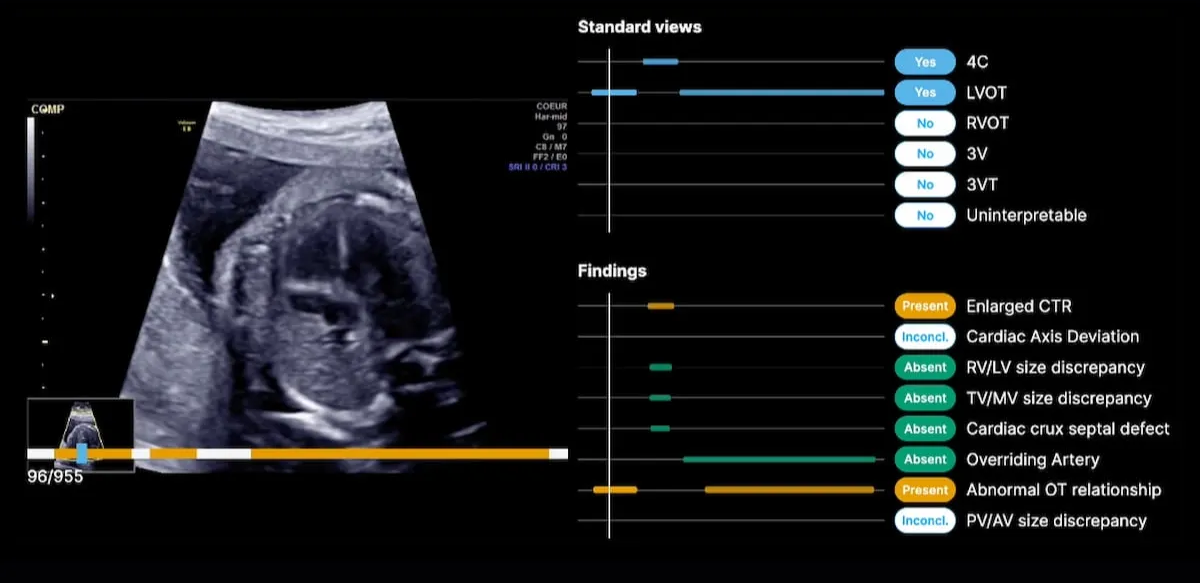

🧠 Prenatal Ultrasound, Reinvented: How BrightHeart AI Catches 90% of Deadly Fetal Heart Defects Before Birth

Enter BrightHeart, a Paris-born startup that set out to solve one of the hardest problems in screening: making expert-level fetal heart exams routine, not exceptional. Instead of trying to replace clinicians, BrightHeart’s AI guides them—step by step—through the ultrasound exam, ensuring completeness, flagging subtle anomalies, and dramatically reducing missed diagnoses.

The results are startling. Detection rates jump from ~30% to over 90%. Exam times shrink. Recalls drop. And for the first time, severe heart disease can be identified before birth—when care pathways, delivery plans, and outcomes can still be changed.